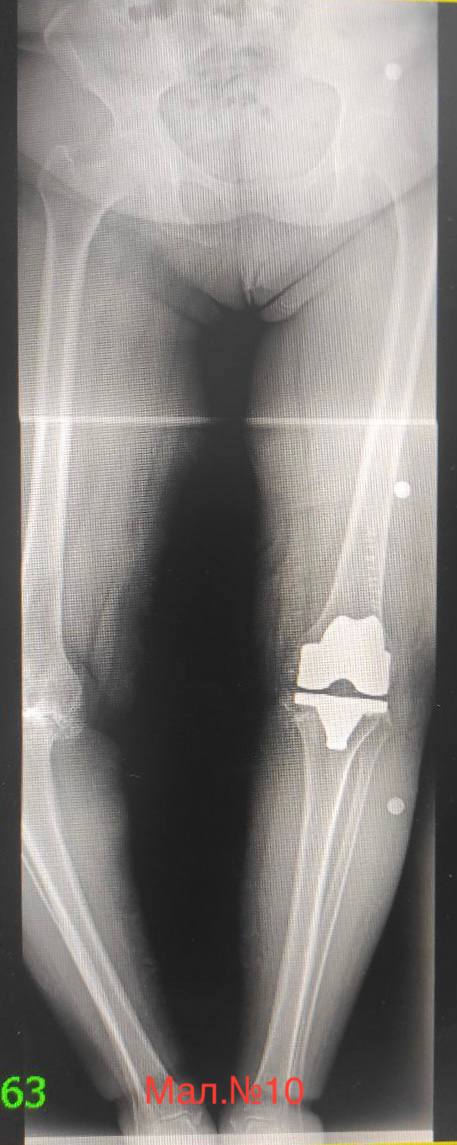

photo_2023-12-13 17.11.37